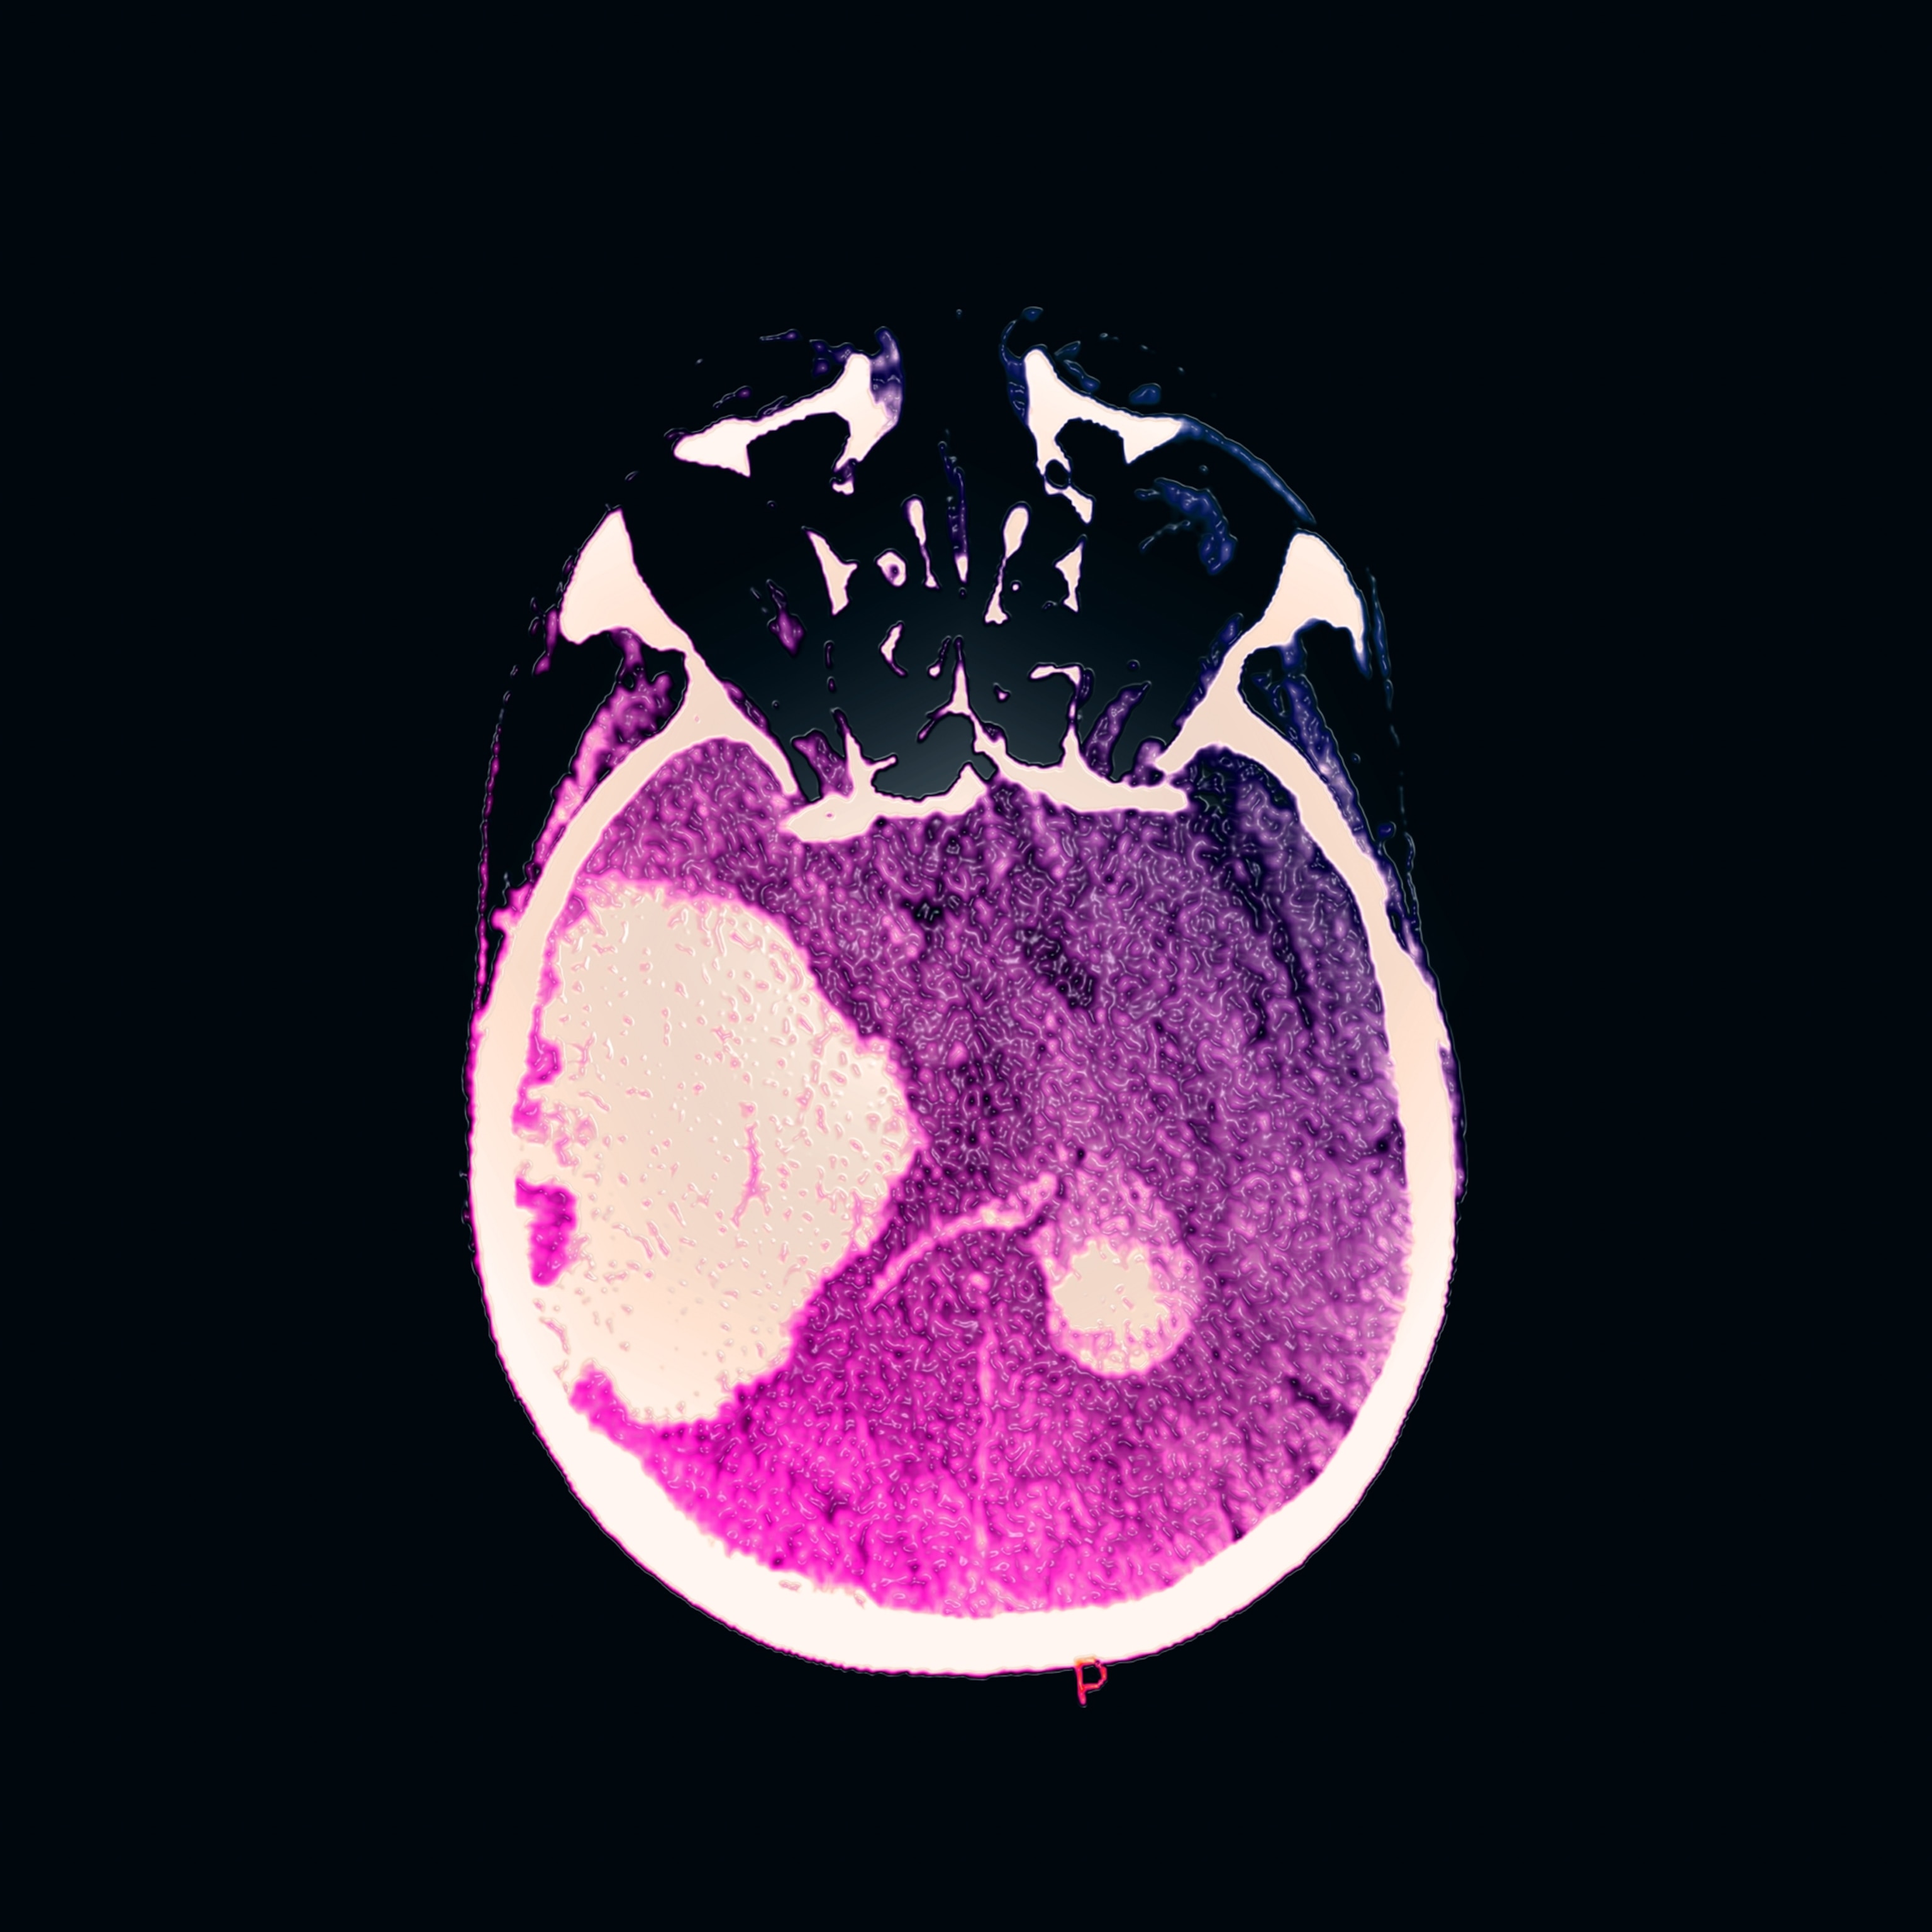

Hemorrhagic strokes—also known as intracerebral hemorrhages (ICH)—occur when a weakened blood vessel ruptures and bleeds into surrounding brain tissue. They account for only 10 to 20 percent of all strokes annually, but are far deadlier and more damaging than the more common ischemic type.

The study analyzed more than 1,600 patients admitted to Massachusetts General Hospital between 2003 and 2019 for spontaneous, non-traumatic brain hemorrhages. About 7 percent were classified as heavy drinkers—those who regularly consume three or more alcoholic drinks a day.

These heavy drinkers were shown to experience hemorrhages about 11 years earlier than their lighter-drinking counterparts—on average, age 60 versus 71. The researchers believe this accelerated timeline is linked to alcohol’s effects on vascular aging and blood vessel fragility.

For instance, compared with light or non-drinkers, these patients had higher blood pressure and lower platelet counts. "Importantly, the brain scans also showed more small-vessel damage and disease," adds Begeti.

The imaging further revealed that heavy drinkers had larger hemorrhages and more frequent intraventricular extension—bleeding that spreads into the brain’s fluid-filled spaces, which is a marker linked to higher mortality. “Together, these findings highlight that heavy alcohol use appears to accelerate vascular aging in the brain,” says Begeti.

While past research has hinted at the connection between heavy alcohol use and vascular aging in the brain, Gurol notes that most earlier studies lacked detailed imaging to reveal the biological mechanisms behind why. “This is the largest study to include CAT scans of the brain in all patients and MRIs in about 75 percent,” Gurol says. This allowed the team to identify structural brain changes and better understand the ways alcohol contributes to bleeding risk.